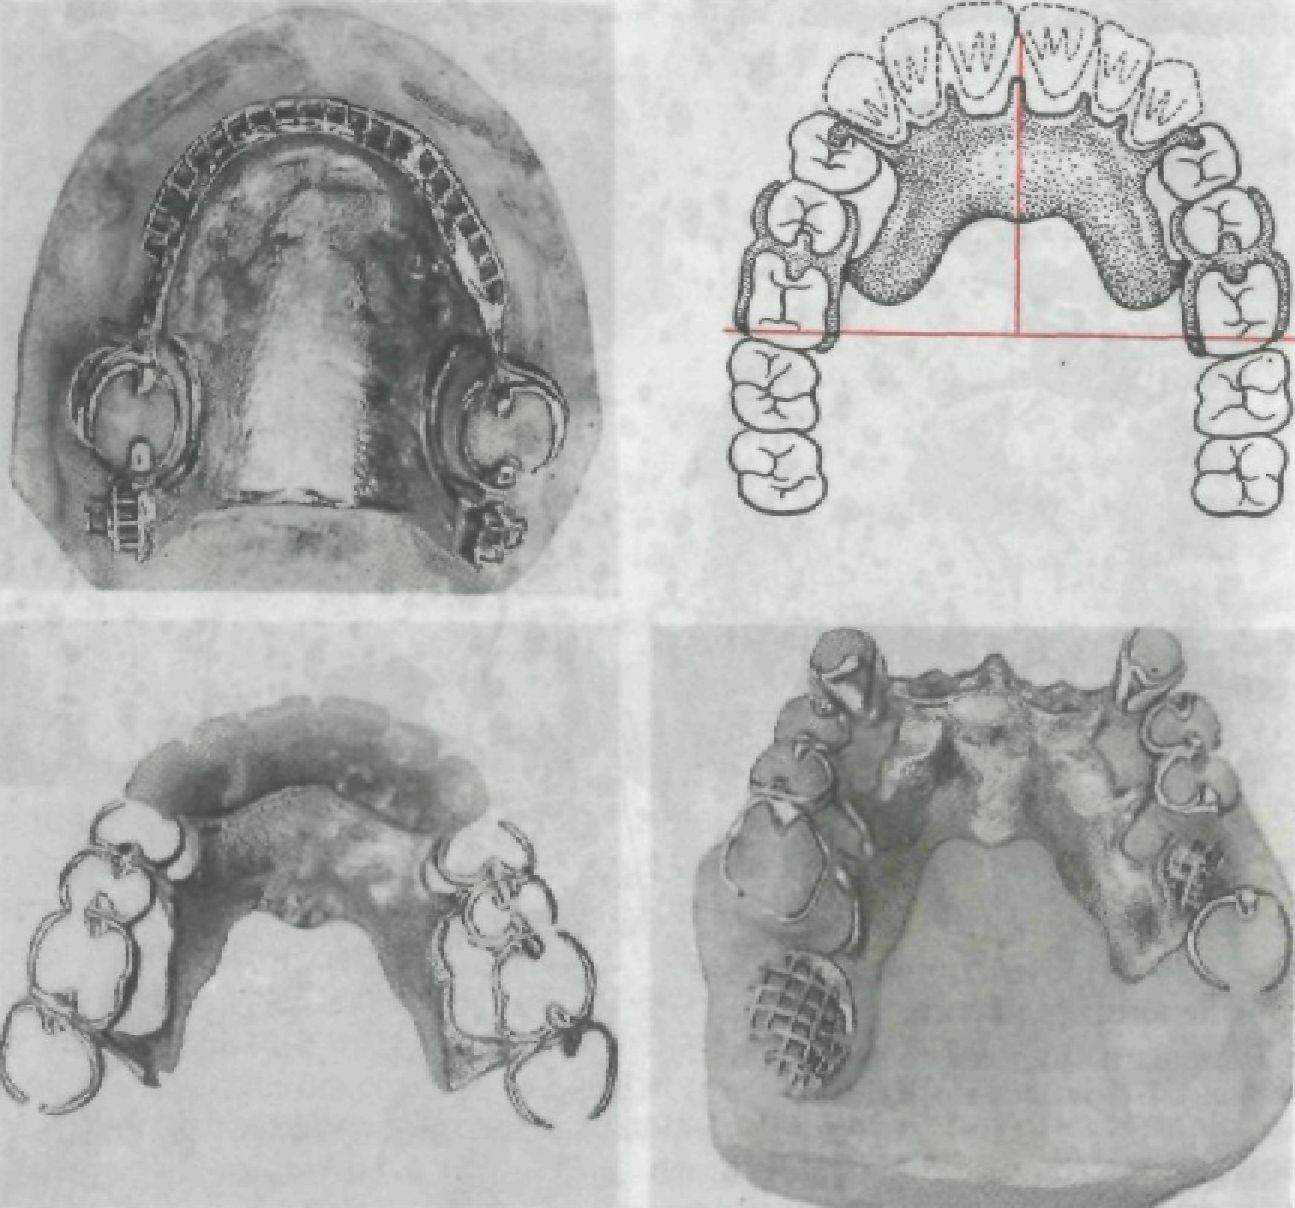

На рис. 131—133 представлены варианты дефектов зубных рядов, варианты врачебных решений по выбору конструкций съемных протезов. Схемы на рисунках позволят студенту самостоятельно осмыслить обоснование выбора конструкции съемного протеза.

Рис. 133. Протезы, применяемые при лечении адентий. Варианты IV класса по Кенеди.